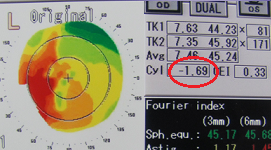

黄斑円孔の手術に関しては、?で記載しましたが、簡単におさらいすると、目の中に器械をいれて、内境界膜という網膜の表層の膜を剥離し、網膜を柔らかくします。その後、目の中に空気を入れてうつ伏せをすることで、円孔の周囲の網膜を浮力で引き寄せて、穴を閉じる。という方法です。